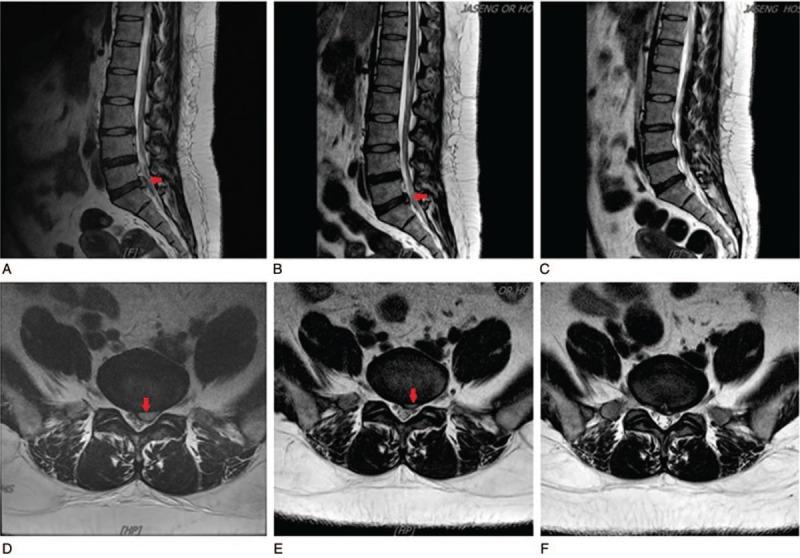

The patient was diagnosed as having discal cysts that compressed the left S1 based on findings of L-spine magnetic resonance imaging (MRI) performed at our hospital.

Spontaneous regression was confirmed in the L-spine MRI follow-up at 36 days and 99 days after the initial test, and the patient underwent once-a-week follow up to examine NRS, Oswestry Disability Index (ODI), EuroQol-5 Dimensions (EQ-5D), and fear-avoidance beliefs questionnaire (FABQ) after 4 weeks, and 2, 3, and 6-month follow-ups after that. The patient was discharged in a painless condition, and she was able to carry on for 5 months without increased pain.

根据我院进行的腰椎磁共振成像(MRI)检查结果,该患者被诊断为左侧S1椎间盘囊肿压迫。

在初次检查后的36天和99天进行的腰椎MRI随访中确认囊肿自发消退,患者在4周后每周接受一次随访,检查NRS、奥斯威斯利残疾指数(ODI)、欧洲五维健康量表(EQ-5D)和恐惧回避信念问卷(FABQ),之后在2个月、3个月和6个月进行随访。患者出院时无痛,能够在5个月内无疼痛加剧情况。